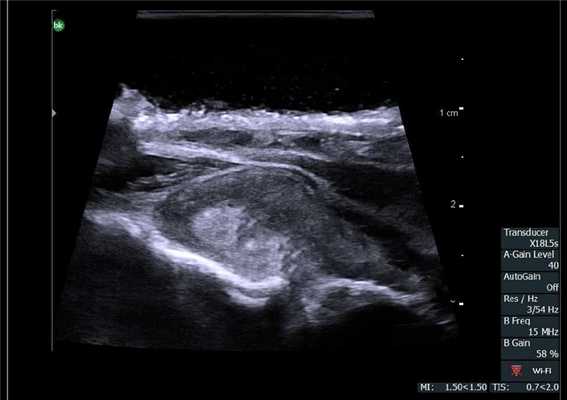

У 5 (41,7%) из 12 пациенток образования в печени имели гиперэхогенную, гомогенную структуру с четкими и ровными контурами размером от 5 до 12 мм в диаметре, которые были интерпретированы как доброкачественные образования печени — гемангиомы (табл. 2). У 4 (33,3%) пациенток образования имели анэхогенную гомогенную структуру, с четкими и ровными контурами, с гладкой внутренней выстилкой и эффектом усиления эхосигнала, размером от 3 до 11 мм в диаметре, и были интерпретированы как кисты. В 3 (25%) случаях в печени были выявлены гипоэхогенные образования солидной гетерогенной структуры с нечеткими, но ровными контурами размером от 10 мм в диаметре (рис. 1) до 22×17×15 мм в одном случае, расположенное на диафрагмальной поверхности печени, которое «самоампутировалось» в процессе исследования и при срочном гистологическом исследовании оказалось метастазом аденогенного рака (рис. 2).

Рис. 1. Эхограмма. Интраоперационное УЗИ печени (стрелкой указан метастаз рака яичника).